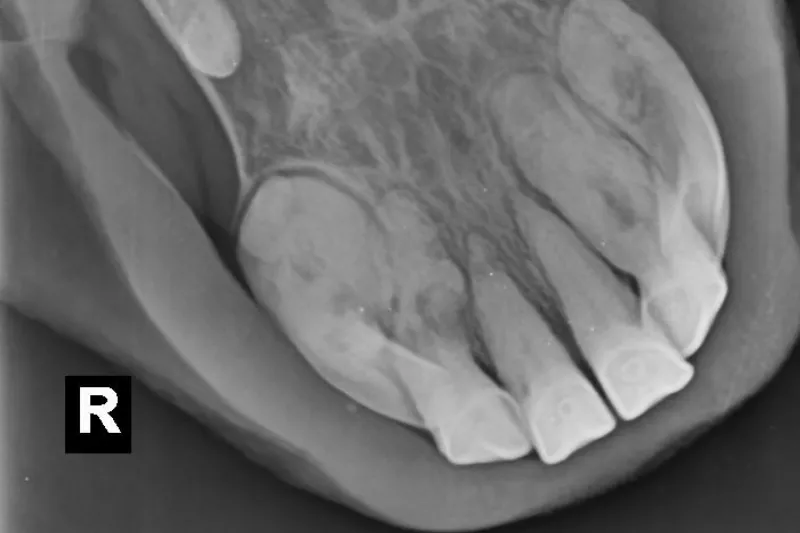

EOTRH is definitively diagnosed on X-rays, usually taken when we see changes to the external appearance of the teeth (gingival recession, swellings over the tooth roots and periodontal disease are commonly associated with the disease) or a change in oral behaviours (difficulty chewing or biting down onto carrots, bad breath, bitting problems, head shaking)¹ EOTRH is a very painful condition due to both the destruction of the normal tooth structure, including potentially the nerve supply to the tooth itself, and also the secondary infection and inflammation.